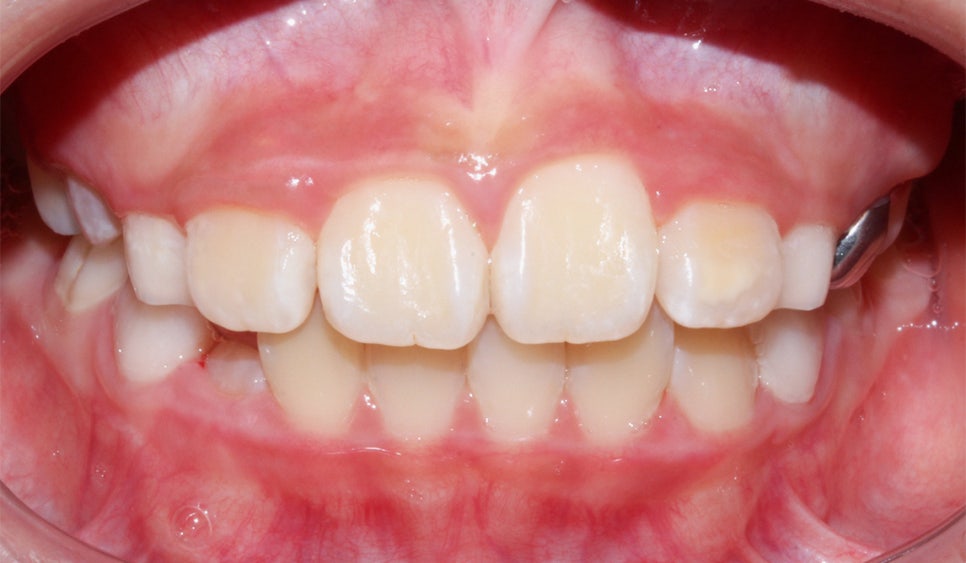

<24개월 교정 완료 모습>

전체적으로 치아가 크게 개선이 되었어요.

저희뿐만 아니라 아이와 보호자 모두

교정 후의 차아 상태를 매우 만족해하셔서

기분이 좋았던 케이스에요